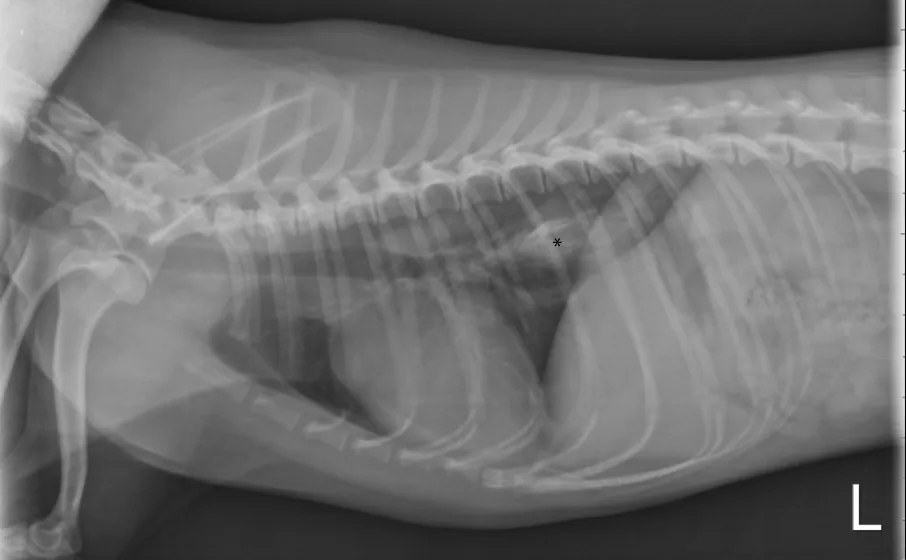

On physical examination, the patient stands in a hunched position and is hypersalivating. Vital parameters (including body temperature) are within normal limits, and the remainder of the examination is normal. Baseline clinical pathology, including CBC and serum chemistry profile, is normal. A mineralized foreign opacity in the caudal esophagus is noted on thoracic radiography (Figure 1).

Left lateral thoracic radiograph of a dog with dysphagia. A mineralized foreign opacity is noted in the caudal esophagus (asterisk).